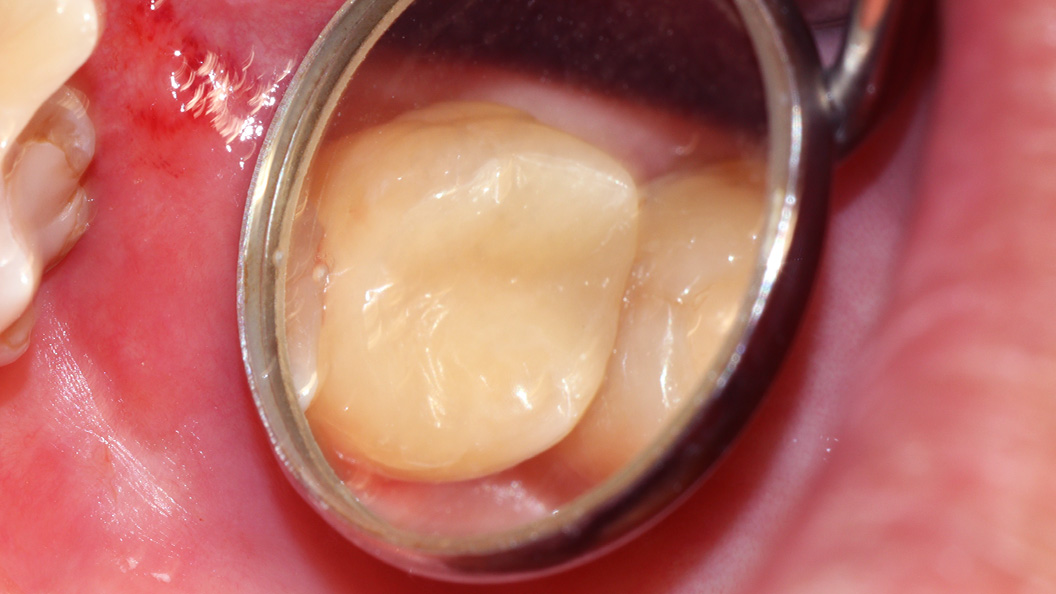

До и после лечения

В клинику «Стоматология Комфорта» обратился пациент с жалобой на выпадение пломбы из моляра верхней челюсти, а также на чувствительность зуба к перепадам температуры и застревание кусочков пищи. В результате осмотра выявлен хронический глубокий кариес зуба 27. Проведено лечение с применением светоотверждаемого композита Эстелайт.

- установка пломбы из светоотверждаемого композита Эстелайт;